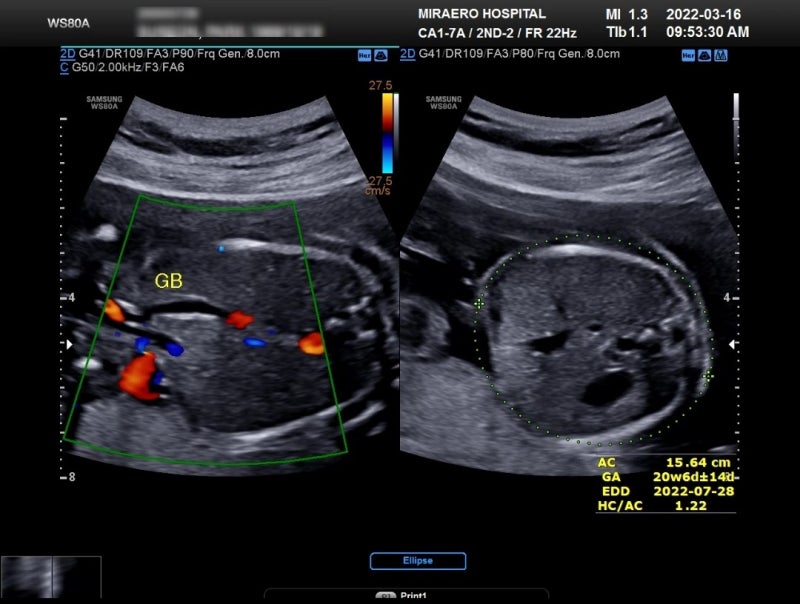

정밀 초음파 태아의 뇌, 폐, 심장, 위장, 신장, 골격에 대한 이상 유무를 조기에 발견하기 때문에 임신 22~23주에 검사 진행 해부학적·구조적 이상의 80~90% 발견 가능 기능적 이상 유무는 불분명하다. 검사시간 : 쌍둥이로 인해 50분정도 보호자 동반불가 / 마미톡 업로드 가능 담당선생님과는 검사결과를 공지(진료실 초음파X) 초음파 전 소변을 1~2시간 이상 참는 것이 좋다

9시에 별관에 있는 영상의학과에 가서 대기 두근거려요.이름을 부르기에 들어가자 안은 생각보다 어둡고 아늑한 분위기의 침대에 올라가 초음파를 보기 시작하는 두 사람이기 때문에 A, B처럼 구분해 본다고 했습니다. A는 왼쪽에 있는 행복이 B는 오른쪽에 있는 축복이

자세는 5번 자세처럼 있다고 하셨어요. 행복이는 밑에 머리가 놓여 있고, 내 머리는 오른쪽 갈비뼈 밑에 있거든요. 그래서 양쪽 갈비뼈가 아팠구나. 한 명은 발로 차고 한 명은 머리로 밀고.얼굴로 확인해서 다행히 머리 크기는 작은 편이고 코와 입 사진도 찍고 있었습니다.언청인지 확인하는 것이라고 했어요. 코도 입도 잘 발달되어 있습니다.옆 라인도 예쁘네요.(고슴도치 사랑)귀도 두 개씩 있는지 확인하고 팔, 다리뼈의 모양과 길이, 뇌, 장기에 물이 고여 있는 곳은 없는지 꼼꼼히 살펴봤습니다.아주 잘 발달되어 있다고 했어요. 훌륭한 복들손과 발가락, 발가락이 5개씩 있는지도 확인하고 얼마나 귀여웠는지 하나씩 확인시켜주는데 웃었어요. 복복(B) 촬영할 때는 발을 너무 차서 촬영이 힘들어서 다른 것을 보고 다시 찍자고 할 정도로 활발했습니다.발길질 야야야야야야.사실 좀 깜짝 놀랐어요. 그때 태동을 느낄 때 행복이는 되게 잘 움직이는데 저는 조용하다고 생각했거든요. 이렇게 잘 움직이다니 둔한 엄마인 것 같아요.드디어 찍은 내 다리! 너의 다리를 찍느라 선생님이 많이 고생하셨다.검사하는 시간은 대략 1시간 정도, 태아의 경우 25~30분의 2이기 때문에 더 시간이 걸렸습니다. 검사실이 어두워서 나중에 졸립니다.선생님이 두 분 다 주수에 맞게 잘 자라고 있고 몸무게도 단테어 수준이라고 하셨어요. 나는 조금 더 무게감이 있는 편이지만 둘 다 비슷한 수준이라 괜찮다.양손의 양도 적당해 문제가 되는 부분은 보이지 않는다.얼마나 고마웠는지, 최근에는 아기가 아프지 않고 건강하게 자라주는 것이 얼마나 고마운 일인지 깨닫고 있습니다.22주차의 개인적인 증상갈비 뼈 아픈 특별한 것은 없지만, 점점 허리와 등이 아파서 있습니다. 아무래도 아기가 커질수록 내 갈비 뼈가 무너지는 건 아닐까… 충분한 휴식을 취해야 할 것 같습니다. 잦은 소변, 새벽 3시 반에는 항상 화장실에 갑니다.도중에 일어나서 물 한잔 더 마시고 자려고 출근 시간!회사에 있을 때도 화장실에도 자주 갑니다. 앉아 있는 시간도 많고, 아기가 크기 때문 방광도 점점 밀리고 있습니다. 민감 보스 임신을 하면 호르몬 변화를 한답니다.사실 저는 그렇게 민감하지 않았습니다. 시험관의 준비를 할 때도 임신한 때도 스트레스를 크게 받지 않고 묵묵히 지내고 있었다고 생각합니다. 남편은 신기하다임신이 체질인가(이라니까!!)너무 걱정도 힘든 생각을 하게 하지도 못했어요.22주째는 설거지가 궁금합니다. 내가 저녁을 준비하면 남편이 설거지를 바로!! 하고 싶은데요, 남편은 뒤로 한다, 내일 아침에 하라고 미루고 있었습니다.나는 주방을 지나갈 때마다 계속 보고 있기 때문에 점점 화가 나서 남편에게 진상 규명을 했습니다.다른 것을 풀어 주는 남편이지만 하고 달라는 것을 신경 쓰지 않도록 하면 좋겠는데요. 무엇인지 입장 차이, 남편 왈:내가 다른 말을 다 하는데, 그것 하나 나중에 하면 안 되야.퇴근하면 피곤한 거라구.본인이 하고 싶은 때가 있고 그 때 하는.기다리라구요.:나는 다른 일을 하고 달라고 안 하는데 설거지를 제때 하고 준다고 하는데, 그것을 하지 않는 거니? 궁금한 설거지, 제가 일도 하고 밥도 만들고 설거지도 해야겠는걸?임산부인데!것도 쌍둥이인데도 잉스타에도 올리고 법석을 떨면서 남편의 지인들이 형부를 무척 싫어하곴다는(흥! 능숙하죠)설거지 때문에 화가 많이 났어요.이렇게 예민했던 건 처음 식기세척기를 사든 해야지.흥! 22주 아기발달활발한 태아 활동 태아는 똑바로 앉아 있거나 손발을 움직여 자세를 자주 바꾼다고 합니다.손가락도 씻고 스스로 숨쉴 수 있도록 양손도 들이마시고 밤과 낮을 구분할 수 있을 정도로 빛의 밝기를 느낄 수 있습니다. 너무 잘 자라고 있는 행복&축복 다음 진료때도 건강하게 다시 만나자.행복을 담아 축복을 담아 복복을 가득 담아